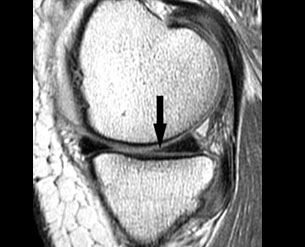

After the special clinical tests are performed, the surgeon may advice for an MRI of the Knee or a diagnostic arthroscopy to confirm the diagnosis. The advantage of a diagnostic arthroscopy over an MRI is that if the pathology is confirmed on arthroscopy the surgeon can go ahead and perform the surgery in the same sitting.